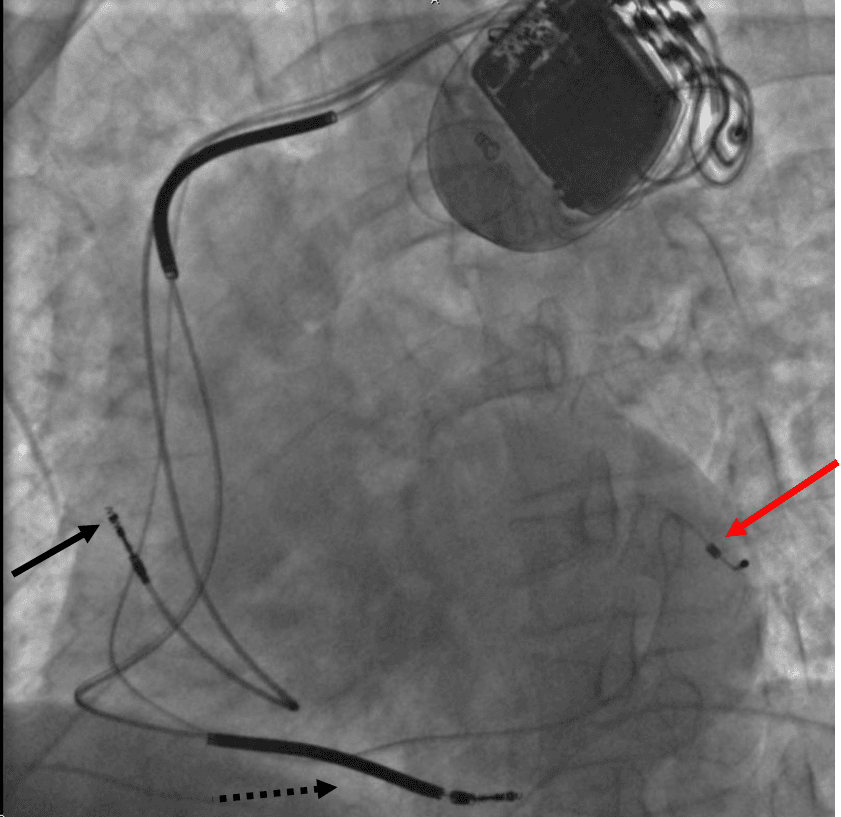

vignette|Stimulateur cardiaque posé pour une resynchronisation cardiaque. La resynchronisation cardiaque est une technique de traitement de l'insuffisance cardiaque par pose d'un stimulateur cardiaque spécial permettant la délivrance d'une stimulation électrique simultanée sur plusieurs points des ventricules. Elle est appelée également stimulation multisite. Cette fonction de resynchronisation peut être couplée à une fonction de défibrillateur automatique implantable, donnant un défibrillateur multi site. Depuis les premières publications de l’équipe française du Val d'Or dès 1995, la stimulation cardiaque multisite s’est imposée comme un traitement incontournable de certains cas d'insuffisance cardiaque systolique. Les premiers stimulateurs multisites étaient de simples stimulateurs cardiaques dont la sortie ventriculaire était dédoublée, permettant de brancher deux sondes à ce niveau. Les premières études se sont surtout attachées à démontrer l’efficacité de la stimulation multisite pour soulager les symptômes. Ainsi, on voit s’améliorer le périmètre de marche, les scores de qualité de vie et la classe NYHA. Par la suite, il a été montré l’amélioration de critères plus objectifs tels que la VO2max et à un moindre degré la fraction d’éjection. Parallèlement le nombre d’hospitalisations pour décompensation cardiaque congestive est réduit. Enfin, en 2009, l’étude Care-HF a montré une réduction de la mortalité par la stimulation multisite Le ventricule gauche se contracte idéalement de manière synchrone, c'est-à-dire, chaque paroi de manière simultanée. Lorsqu'une ou plusieurs parois se contractent de manière retardé, l'efficacité mécanique est bien moindre et le débit cardiaque peut chuter de ce fait. Cet asynchronisme se traduit de manière électrique par un bloc de branche sur l'électrocardiogramme, c'est-à-dire, par un élargissement du QRS, onde en rapport avec la dépolarisation des ventricules. En imagerie, cet asynchronisme peut être directement visualisé en échocardiographie ou en scintigraphie.